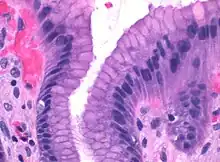

![]() Microscopic section of gastric mucosa. Foveolar cells can be seen at top of the image lining the surface and pits | |

Foveolar cells line the surface of the stomach, the gastric pits, and the top part of gastric glands: the neck. They constitute a simple columnar epithelium, as they form a single layer of cells and are taller than their width. Depending on their location, foveolar cells can be divided in two groups: surface mucous cells, which line the surface and the gastric pits; and mucous neck cells, which are a part of the neck of gastric glands along parietal cells.[2]: 257

Surface mucous cells have large quantities of mucin granules in their apical (top) surface and project short microvilli into the lumen of the stomach.[2]: 257 Mucins are large glycoproteins that give the mucus its gel-like properties.[3] As mucins are lost during routine histology preparation, they stain pale, but if preserved correctly the cells stain strongly with special techniques like PAS or toluidine blue, the last representing the anionic nature of foveolar cell secretions. Below the mucin granules, surface mucous cells have a Golgi apparatus, the nucleus, and small amounts of rough endoplasmic reticulum.[4]: 577 Mucous neck cells are located within gastric glands, interspersed between parietal cells. These are shorter than their surface counterpart and contain lesser quantities of mucin granules in their apical surface.[4]: 578